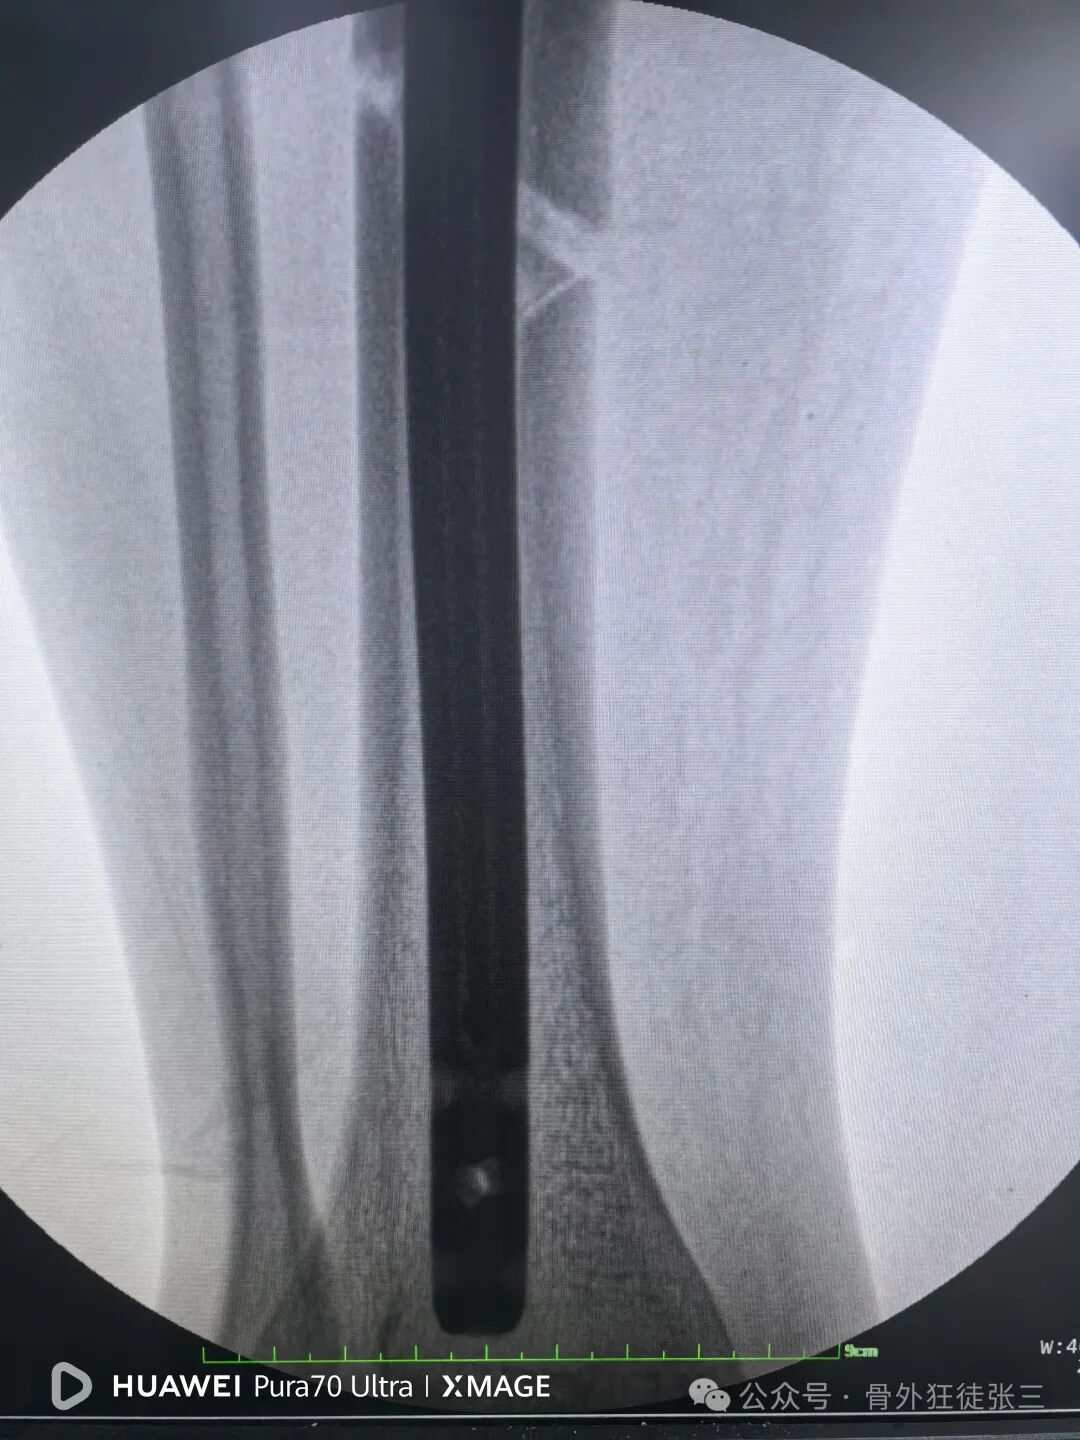

6,扩髓时,不需要复位,但是需要扩到过狭窄部位,不要一杆子扩到底,容易不居中。

7,髓内钉本身就是复位工具,在此时依靠髓内钉+手法,几乎都能顺利复位。